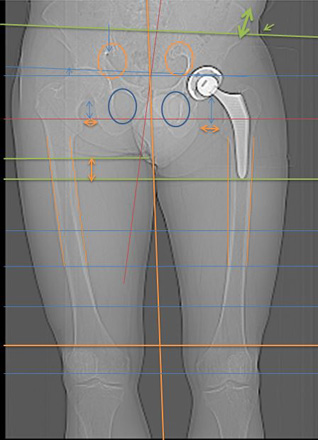

Hüft mit Strichen Pfeilen Kreise sichtbar gemacht

Oberkörper weicht trotz Hüftgelenk Ersatz blau eingesetzte Striche aus.

Anhand der Gesässfalten wird auch der Beckentiefstand ersichtlich.

Über die Grüne Linie sieht man wie die rechte Seite geknickt wird.

Auf der linken Seite wird die Überdehnungsspannung sichtbar.

Würde die Ganz-Körper-Statik Vermessung eingesetzt, würde die Diagnose schnell und präzise die Ausweichhaltungen aufzeigen.

Würde die Ganz-Körper-Statik Vermessung bei den bildgebenden Verfahren eingesetzt, könnten Fehldiagnosen verhindert werden. Dies würde die Ursache der Skelett Ausweichhaltungen als Ursache der Muskelfehlspannungen aufzeigen.

1.7

Trotz dem wurde das andere Hüftgelenk auch noch ausgewechselt.

Trotz Operationen sind die Schmerzen geblieben.

Beachtet man das Becken und die Gelenk-Stellungen sieht man nun auf der rechten Seite eine Verdrehung des Beckenlochs.

Der Beckenspalt ist immer noch hochgezogen. Durch die Verdrehung quetscht nun die linke Seite.

Man hat die Belastung verschoben.

Bei der Statik Kontrolle wurde der Beckentiefstand und der damit verbundenen seitlichen Oberkörper- Ausweichhaltung nicht beachtet.

Würde die Ganz-Körper-Statik Vermessung bei den bildgebenden Verfahren eingesetzt, könnten Fehldiagnosen verhindert und zudem viele Kosten gespart werden. Dies würde die Ursache der Skelett Ausweichhaltungen als Ursache der Muskelfehlspannungen aufzeigen.

Um auch die Ursache der Beschwerden aufzudecken, wird der Einbau der Ganzkörperstatik und des Hebelgesetzes benötigt, damit auch reproduzierbar die Gesamtkörperstatik berücksichtigt werden kann.